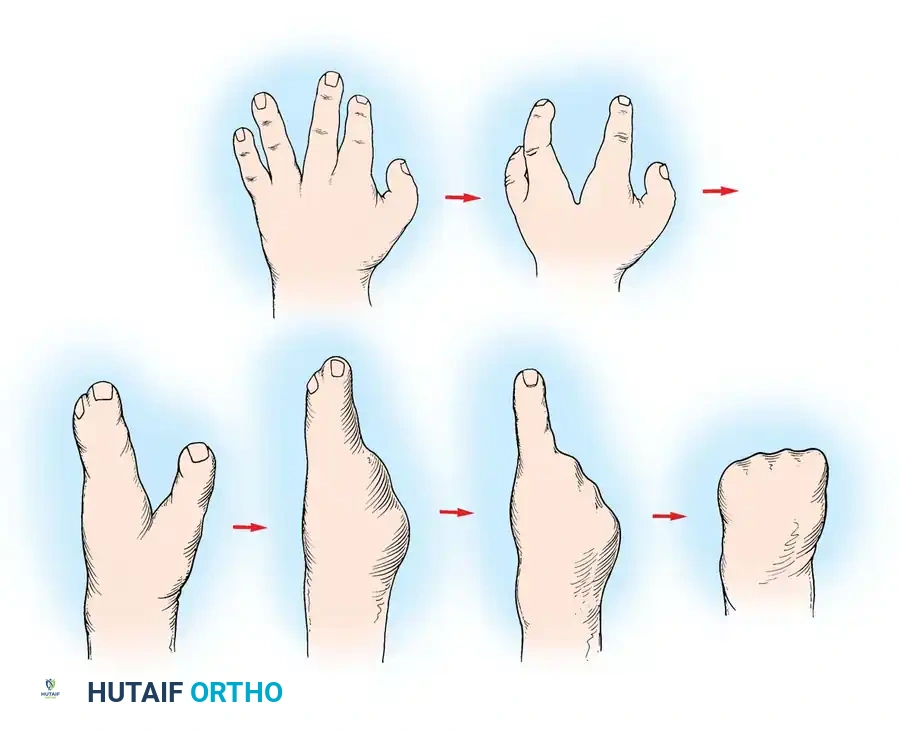

A newborn presenting with a transverse deficiency typically exhibits a slightly bulbous, well-padded stump. In more distal deficiencies, rudimentary, vestigial digital "nubbins" are frequently observed.

Fig. 76-2 Failure of formation (digital nubbins). The presence of functional wrist motion allows the limb to be used effectively as an assisting hand.

Hypoplasia of the more proximal musculature is a key clinical finding that helps differentiate true transverse deficiencies from amputations caused by congenital constriction band syndrome (amniotic band sequence). In the most common presentation—the upper forearm amputation—the forearm is usually no more than 7 cm long at birth and will reach a maximum length of approximately 10 cm by skeletal maturity.

In midcarpal amputations (the second most frequent level), the rudimentary digital remnants are almost always nonfunctional. However, because the radiocarpal joint is preserved, pronation and supination are usually possible, providing a highly functional assisting limb. Cognitive development and intelligence in these children are generally normal.

1. 3 to 6 Months (Sit to Fit): A passive plastic mitten prosthesis is introduced once the child achieves independent sitting balance. This provides stability during sitting and assists in pulling to a stand.

2. 12 to 18 Months: The passive mitten is exchanged for an actively opened, plastisol-covered split hook. A Child Amputee Prosthetic Program (CAPP) terminal device may be substituted. Training with the functional device begins immediately.

3. 2 to 4 Years: A myoelectrical prosthesis may be considered. Studies have shown these to be highly useful and appropriate for preschool-aged children, offering superior cosmesis and intuitive grip control.

Surgical Warning: Prosthetic management for midcarpal amputations remains controversial. The long, below-elbow stump is exceptionally useful for stabilizing objects and bimanual function because it retains native sensibility. Sacrificing terminal sensibility for a cosmetic artificial hand must be carefully weighed against the functional loss.